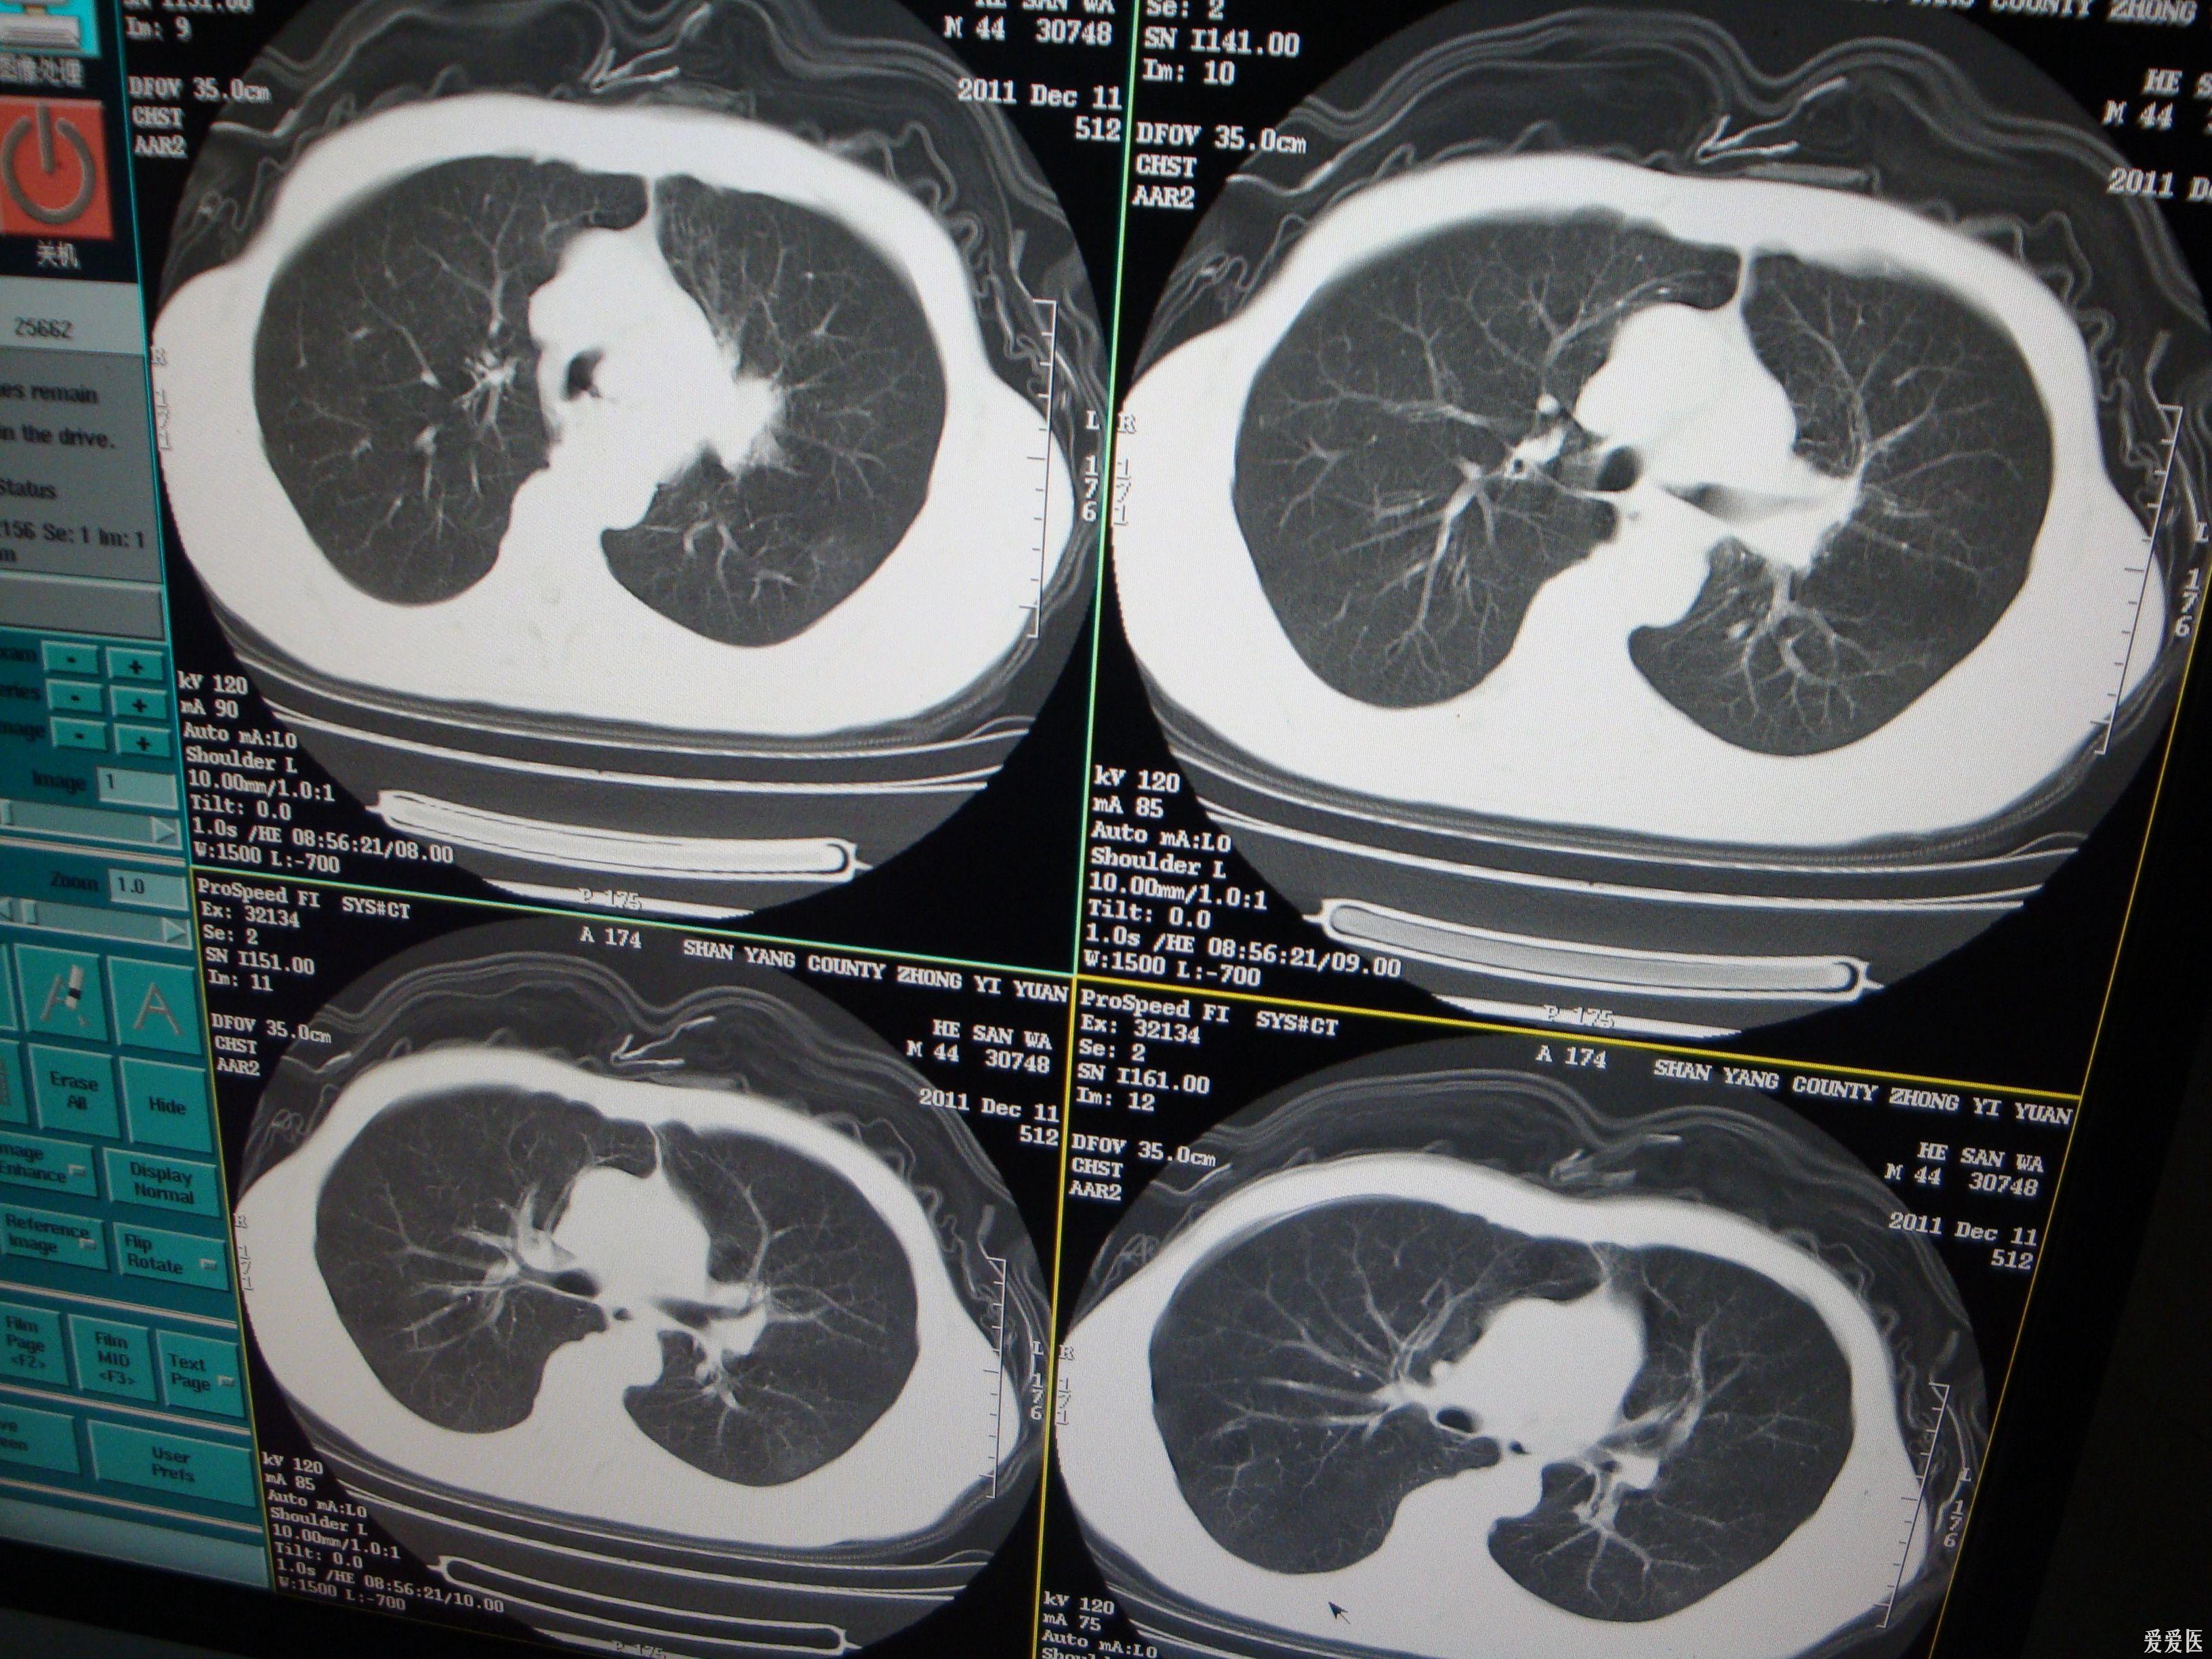

肺结核与肺癌的ct特征性表现及鉴别

肺结核与肺癌像"真假美猴王,医生教你用ct片当放大镜,找不同

华夏览雄 就来和你聊聊「肺炎,肺癌,肺结核在 ct 及胸片上的区别